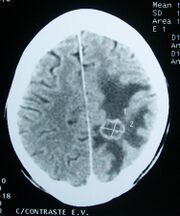

Imaging

CT scan of a brain tumor, with its diameters marked as an X. There is hypoattenuating (dark) peritumoral edema in the surrounding white matter, with a "finger-like" spread.

Medical imaging plays a central role in the diagnosis of brain tumors. Early imaging methods – invasive and sometimes dangerous – such as pneumoencephalography and cerebral angiography have been abandoned in favor of non-invasive, high-resolution techniques, especially magnetic resonance imaging (MRI) and computed tomography (CT) scans,[38] though MRI is typically the reference standard used.[41] Neoplasms will often show as differently colored masses (also referred to as processes) in CT or MRI results.[citation needed]